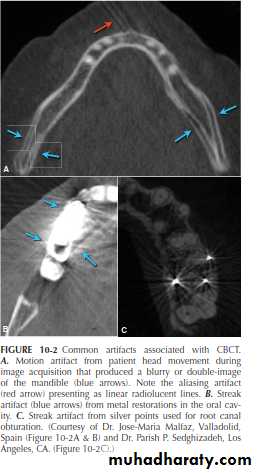

pathological conditions. Hardware and software parameters also heavily influence image quality and resolution. CBCT, like other radiographic modalities, can also contain artifacts and noise that make evaluation and interpretation difficult in some cases. Common artifacts to be aware of include noise, aliasing, scatter and beam hardening, motion artifact, and finally streak artifact that usually results from metal or high density restorations in the oral cavity such as metal crowns, orthodontic appliances, amalgam fillings, separated instruments and tooth, and root canal filling materials